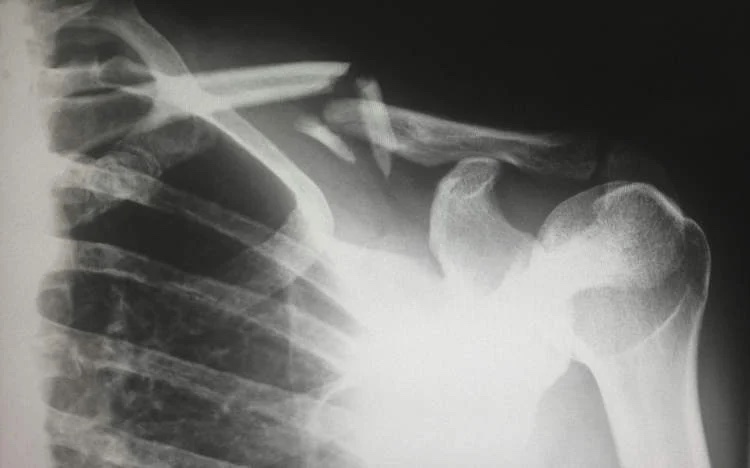

Các bác sĩ tại Bệnh viện Y học cổ truyền XinDu, Thành Đô, Trung Quốc, gần đây đã ghi nhận trường hợp một nữ bệnh nhân 48 tuổi bị gãy xương chỉ vì vô tình lăn mình trên giường.

Ảnh minh hoạ: Unsplash

Theo trang Oddity Central (Anh), Tiến sĩ Long Shuang, người trực tiếp theo dõi ca bệnh, cho biết xét nghiệm cho thấy bệnh nhân có mức vitamin D cực kỳ thấp. Tình trạng thiếu hụt nghiêm trọng này đã đẩy nhanh quá trình loãng xương, khiến xương của cô trở nên yếu đến mức chỉ một chuyển động nhẹ cũng gây ra gãy.